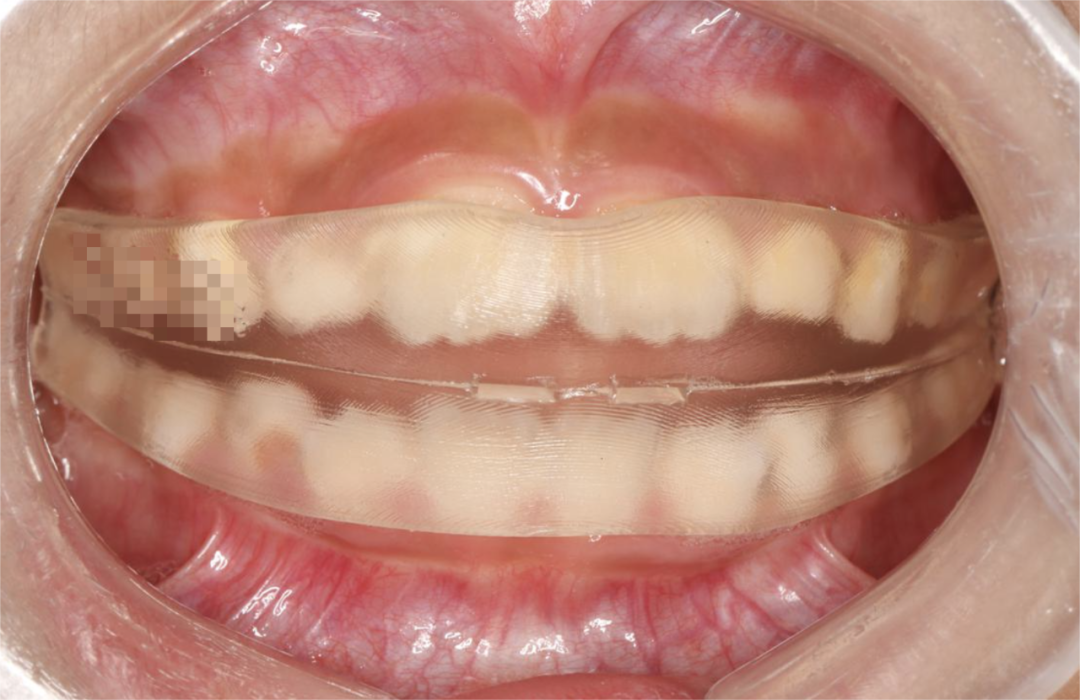

但是乳牙期孩子闭锁性深覆合,不太适合用一些过大的矫治力,通常我会用个性化定制的肌功能矫治器,我们可以做模型扫描,把上牙压低同时牙根往里压。

那这个时候我会设定成为垂直向会压低2个毫米,牙根我会设定成为压入4个毫米,下牙垂直向压低3个毫米,那同时牙齿矫正过程中后牙还要升高,这是我们设计个性化肌功能矫治器,一个最重要的指标。

那么在功能矫正器的引导下,随着孩子牙齿逐步的更换,就可以调整牙的角度,使骨骼结构和牙齿发育达到正常生长。